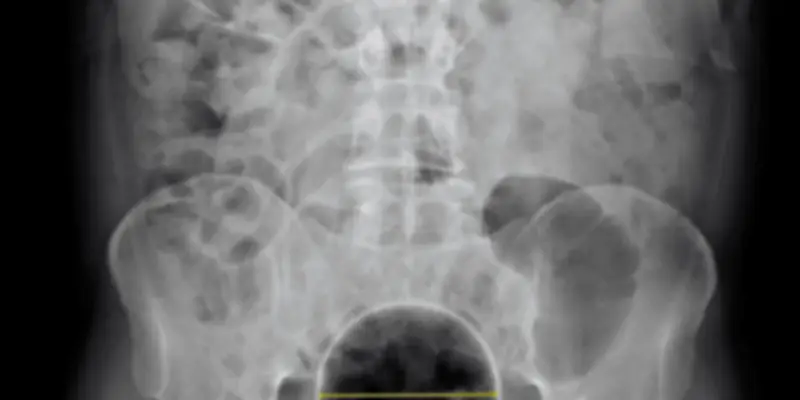

La polyembolokoilamanie est une affection caractérisée par la présence de multiples corps étrangers dans les vaisseaux sanguins, entraînant des complications sévères. Elle nécessite souvent des opérations répétées pour retirer ces obstructions, ce qui peut épuiser les ressources médicales et affecter la qualité de vie des patients.

Dans ce cas spécifique, le patient a été suivi de près par une équipe multidisciplinaire, comprenant des chirurgiens, des radiologues et des spécialistes en médecine interne. Son histoire illustre la nécessité d'une approche coordonnée pour gérer les récidives et prévenir les risques associés.